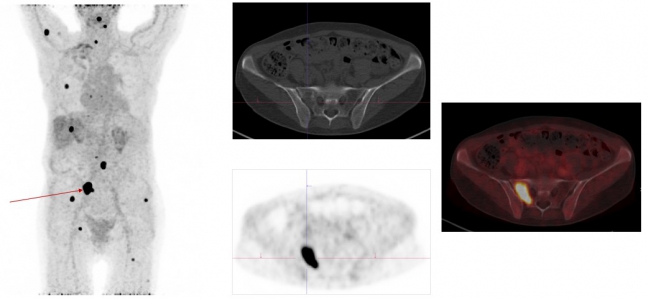

Exemplary case study on Ga-68-FAPI-PET/CT diagnostics: